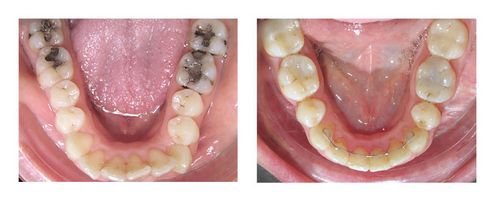

Ce traitement sans difficulté orthodontique (6 mois de traitement) a consisté à avancer les incisives centrales supérieures et les incisives inférieures. La finesse des gencives à l’arcade inférieure a justifié, avant d’entreprendre le travail d’alignement, un apport de gencive en regard des incisives inférieures. En effet, l’avancée de ces dernières peut dans cette situation affiner et donc fragiliser les gencives.

Une contention de longue durée est essentielle après ce type de traitement orthodontique, car les lèvres toniques exercent une force de recul sur les dents devant, source de récidive.